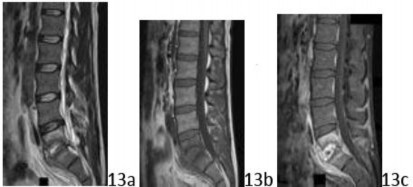

11. # 13a 13b 13c The MRI scans shown in Figures 13a through 13c show findings that are classic and, in combination on the MRI sequences, are pathognomonic for what diagnosis?

DISCUSSION: The sagittal MRI sequences show findings that are classic for diskitis. The T2 image (Figure 13a) has a bright signal appearance within the disk space (free water) consistent with pus. On the T1 image (Figure 13b), the disk and vertebral bony margins appear dark with uniform signal across the disk that results in loss of the distinction between disk and vertebral body. Lastly, on T1, fat suppressed with gadolinium (Figure 13c), the abscess noted on T2 is now dark with a surrounding rim of enhancement (hypervascularity) that includes the adjacent vertebral bodies.

Although an advanced degenerative disk can

appear with a fluid signal within the disk space, the surrounding hypervascularity or obliteration of the distinct margins of the disk is not expected. The Preferred Response to Question # 13 is 4.